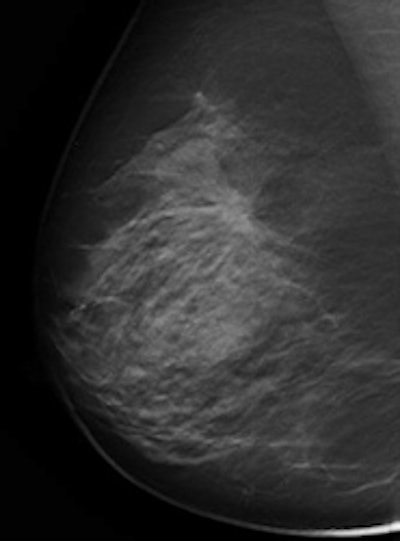

The value of annual mammography screening remains controversial, but for the most part radiologists agree on its utility. With the development of full-field digital mammography, even more cancers are detected, especially in women with dense breasts. The major drawback, however, is "the difficulty of finding and discerning a subtle change against the complex background of the glandular tissue, a particular issue for younger premenopausal women with a so-called dense glandular background pattern," wrote Dr. Matthew Wallis, a consultant radiologist and the director of the Cambridge and Huntingdon Breast Screening Service in the U.K. (Radiol, 24 January 2012, online first).

With tomosynthesis, low-dose images are obtained over a limited arc, and the projections are mathematically reconstructed into a series of sections with the hope that specificity and sensitivity will be improved. Initial work using tomosynthesis as an add-on to conventional 2D mammography suggested the potential for substantial improvements in specificity, the authors noted. They compared the diagnostic accuracy of 2D digital mammography with that of two-view (mediolateral and craniocaudal) and single-view (mediolateral oblique) tomosynthesis in an observer study involving two institutions: Cambridge and Capio St Göran's Hospital in Stockholm.

Ten accredited readers classified 130 women with breast density of 2 to 4 using 2D mammography and two-view tomosynthesis. Another 10 reviewed the same cases using 2D mammography but with single-view tomosynthesis.